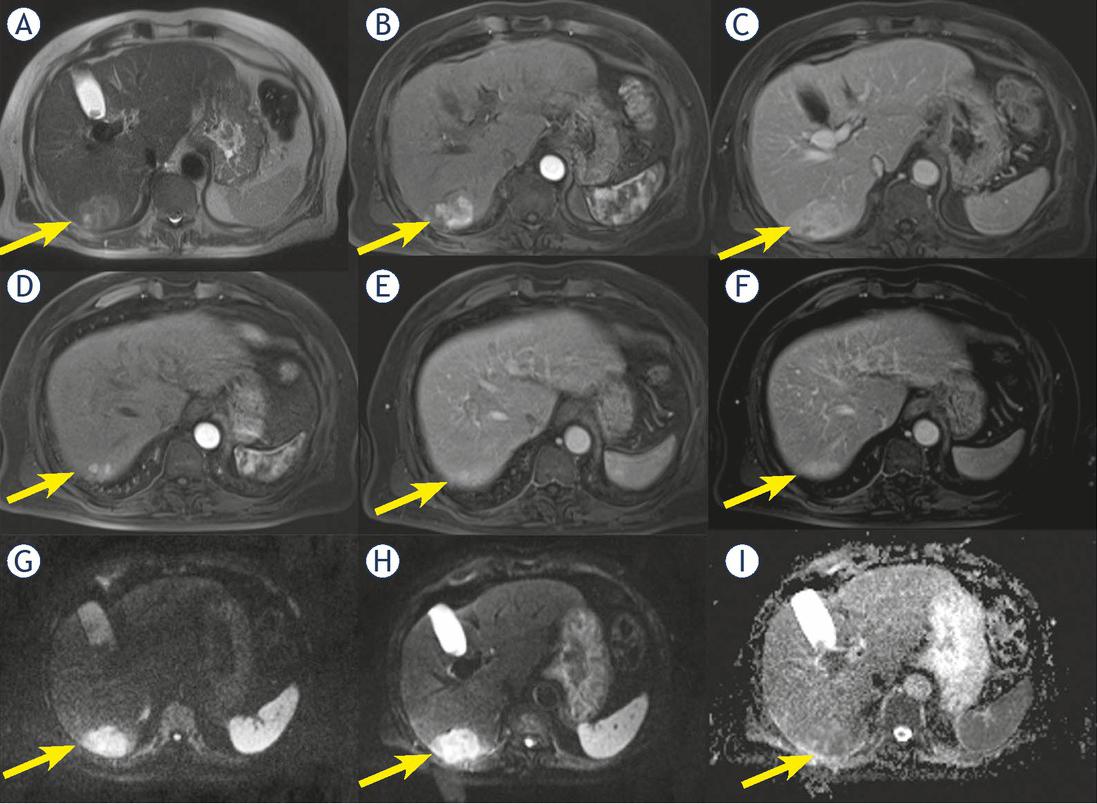

Man 69 y with combined hepatocellular-cholangiocarcinoma (cHCC-CCA) on VI hepatic segment. MRI study. The nodule shows inhomogeneous hyperintense signal (arrow) in T2-W sequence (A) and progressive pattern of enhancement (arrow) during arterial (B) and portal (C) phase of contrast study. In (D, E and F) arrow shows a nodule satellite. Restricted diffusion (arrow) in diffusion weighted imaging (DWI) (G, H and I) sequence.

In ten patients (16.1%) we found satellite nodules (neighboring micrometastases), among them 7 were cHCC-CCA (63.6% of cHCC-CCA) (Figure 5) and 3 (5.9% of HCC) were true HCC.

Progressive contrast enhancement: nine (14.5%) patients showed a progressive contrast enhancement; among them 7 were cHCC-CCA (63.6% of cHCC-CCA) (Figure 4) and 2 (3.9% of HCC) true HCC.